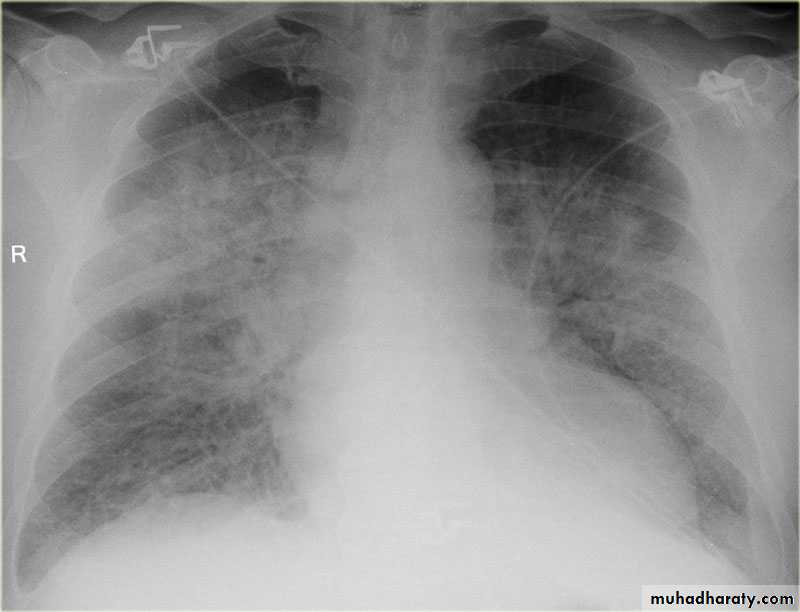

Bat wing sign ( alveolar pulmonary edema)CXR of adult male, PA view shows:Bat wing sign, Cardiomegaly